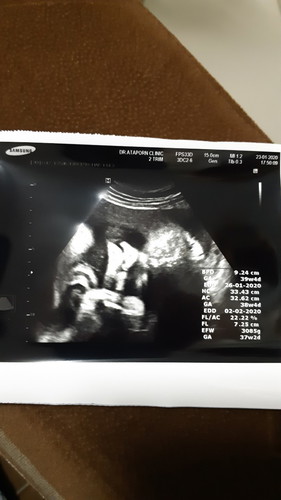

ท้อง 35 วีคกับน้ำหนักลูก

ตอนนี้ท้อง 35 วีคแล้วค่ะ น้ำหนักลูกคือ 3085 แล้ว มีแม่ท่านไหน นน. ลูกเยอะแบบนี้บ้างคะ แล้วเราจะคลอดเองได้ไหม ตัวใหญ่แบบนี้ แพลนว่าตั้งใจจะคลอดเอง ตอนนี้ไม่แน่ใจแล้วว่าจะทำได้ไหม